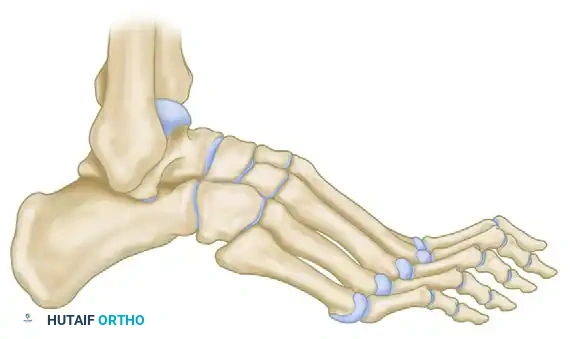

Lateral schematic demonstrating the planned dorsal closing wedge osteotomies at the proximal metaphysis of the metatarsals.

Detail of the osteotomy execution. Note the preservation of the plantar cortex to create a greenstick hinge.

Closure of the dorsal gaps. The greenstick fracture of the plantar cortex allows for elevation of the metatarsal heads, flattening the longitudinal arch.

Postoperative lateral skeletal representation demonstrating a restored, plantigrade alignment following successful closing wedge osteotomies.